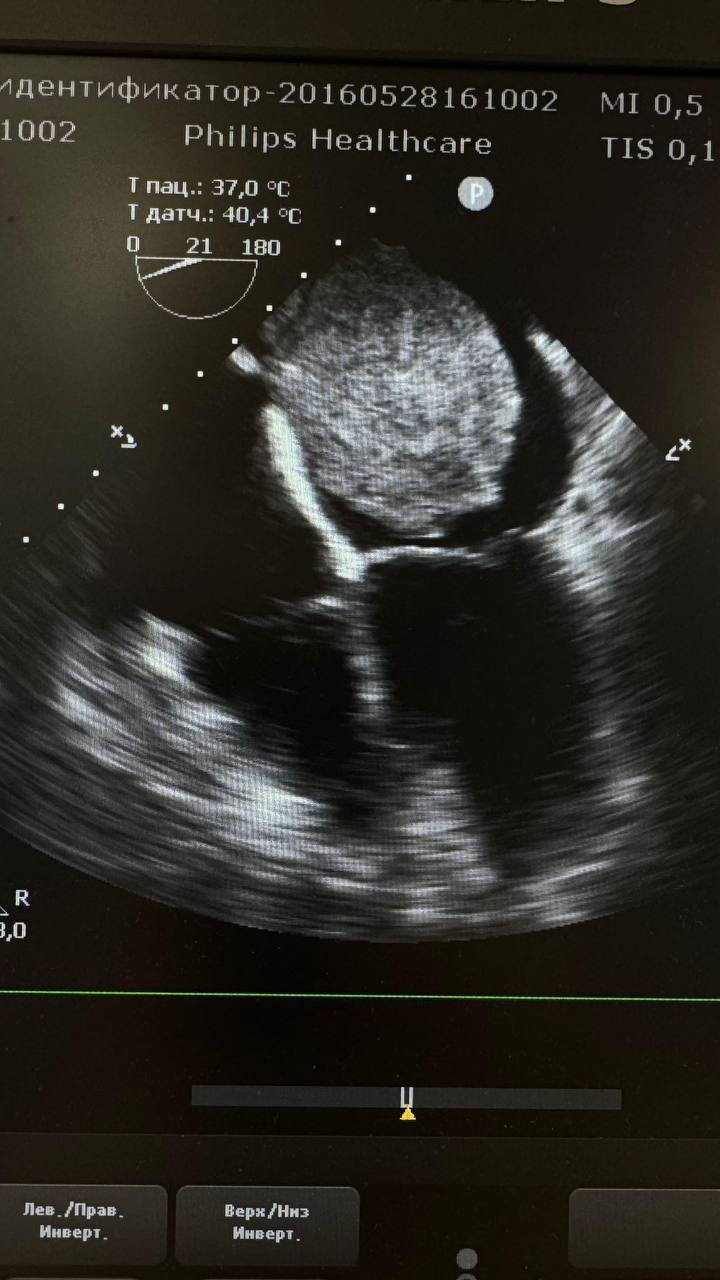

В Дагестанском центре кардиологии и сердечно-сосудистой хирургии в Махачкале провели уникальную операцию. 55-летней пациентке удалили крупную опухоль, которая более двух лет вызывала тяжелую одышку.

Диагноз долгое время оставался неясным, а в сентябре состояние женщины резко ухудшилось: нехватку воздуха она стала ощущать даже при минимальной нагрузке. Опухоль была обнаружена только с помощью УЗИ сердца.

В декабре пациентку экстренно госпитализировали и прооперировали. После хирургического вмешательства её состояние стабилизировалось, она чувствует себя удовлетворительно, получает терапию и готовится к выписке.